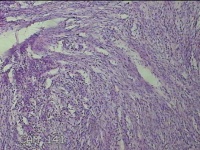

子宫肌瘤结节

多发性子宫肌瘤 继发性不孕症 子宫Ⅰ度脱垂 高脂血症 胆囊息肉

一般病史

发现子宫肌瘤4年余,继发不孕3年。

标本名称

大体所见

灰白暗红色圆形肿物10x9x2.8㎝九个,表面糜烂,切面均为灰白色结节状或编织状,质中。

良性病变。

考虑平滑肌瘤。